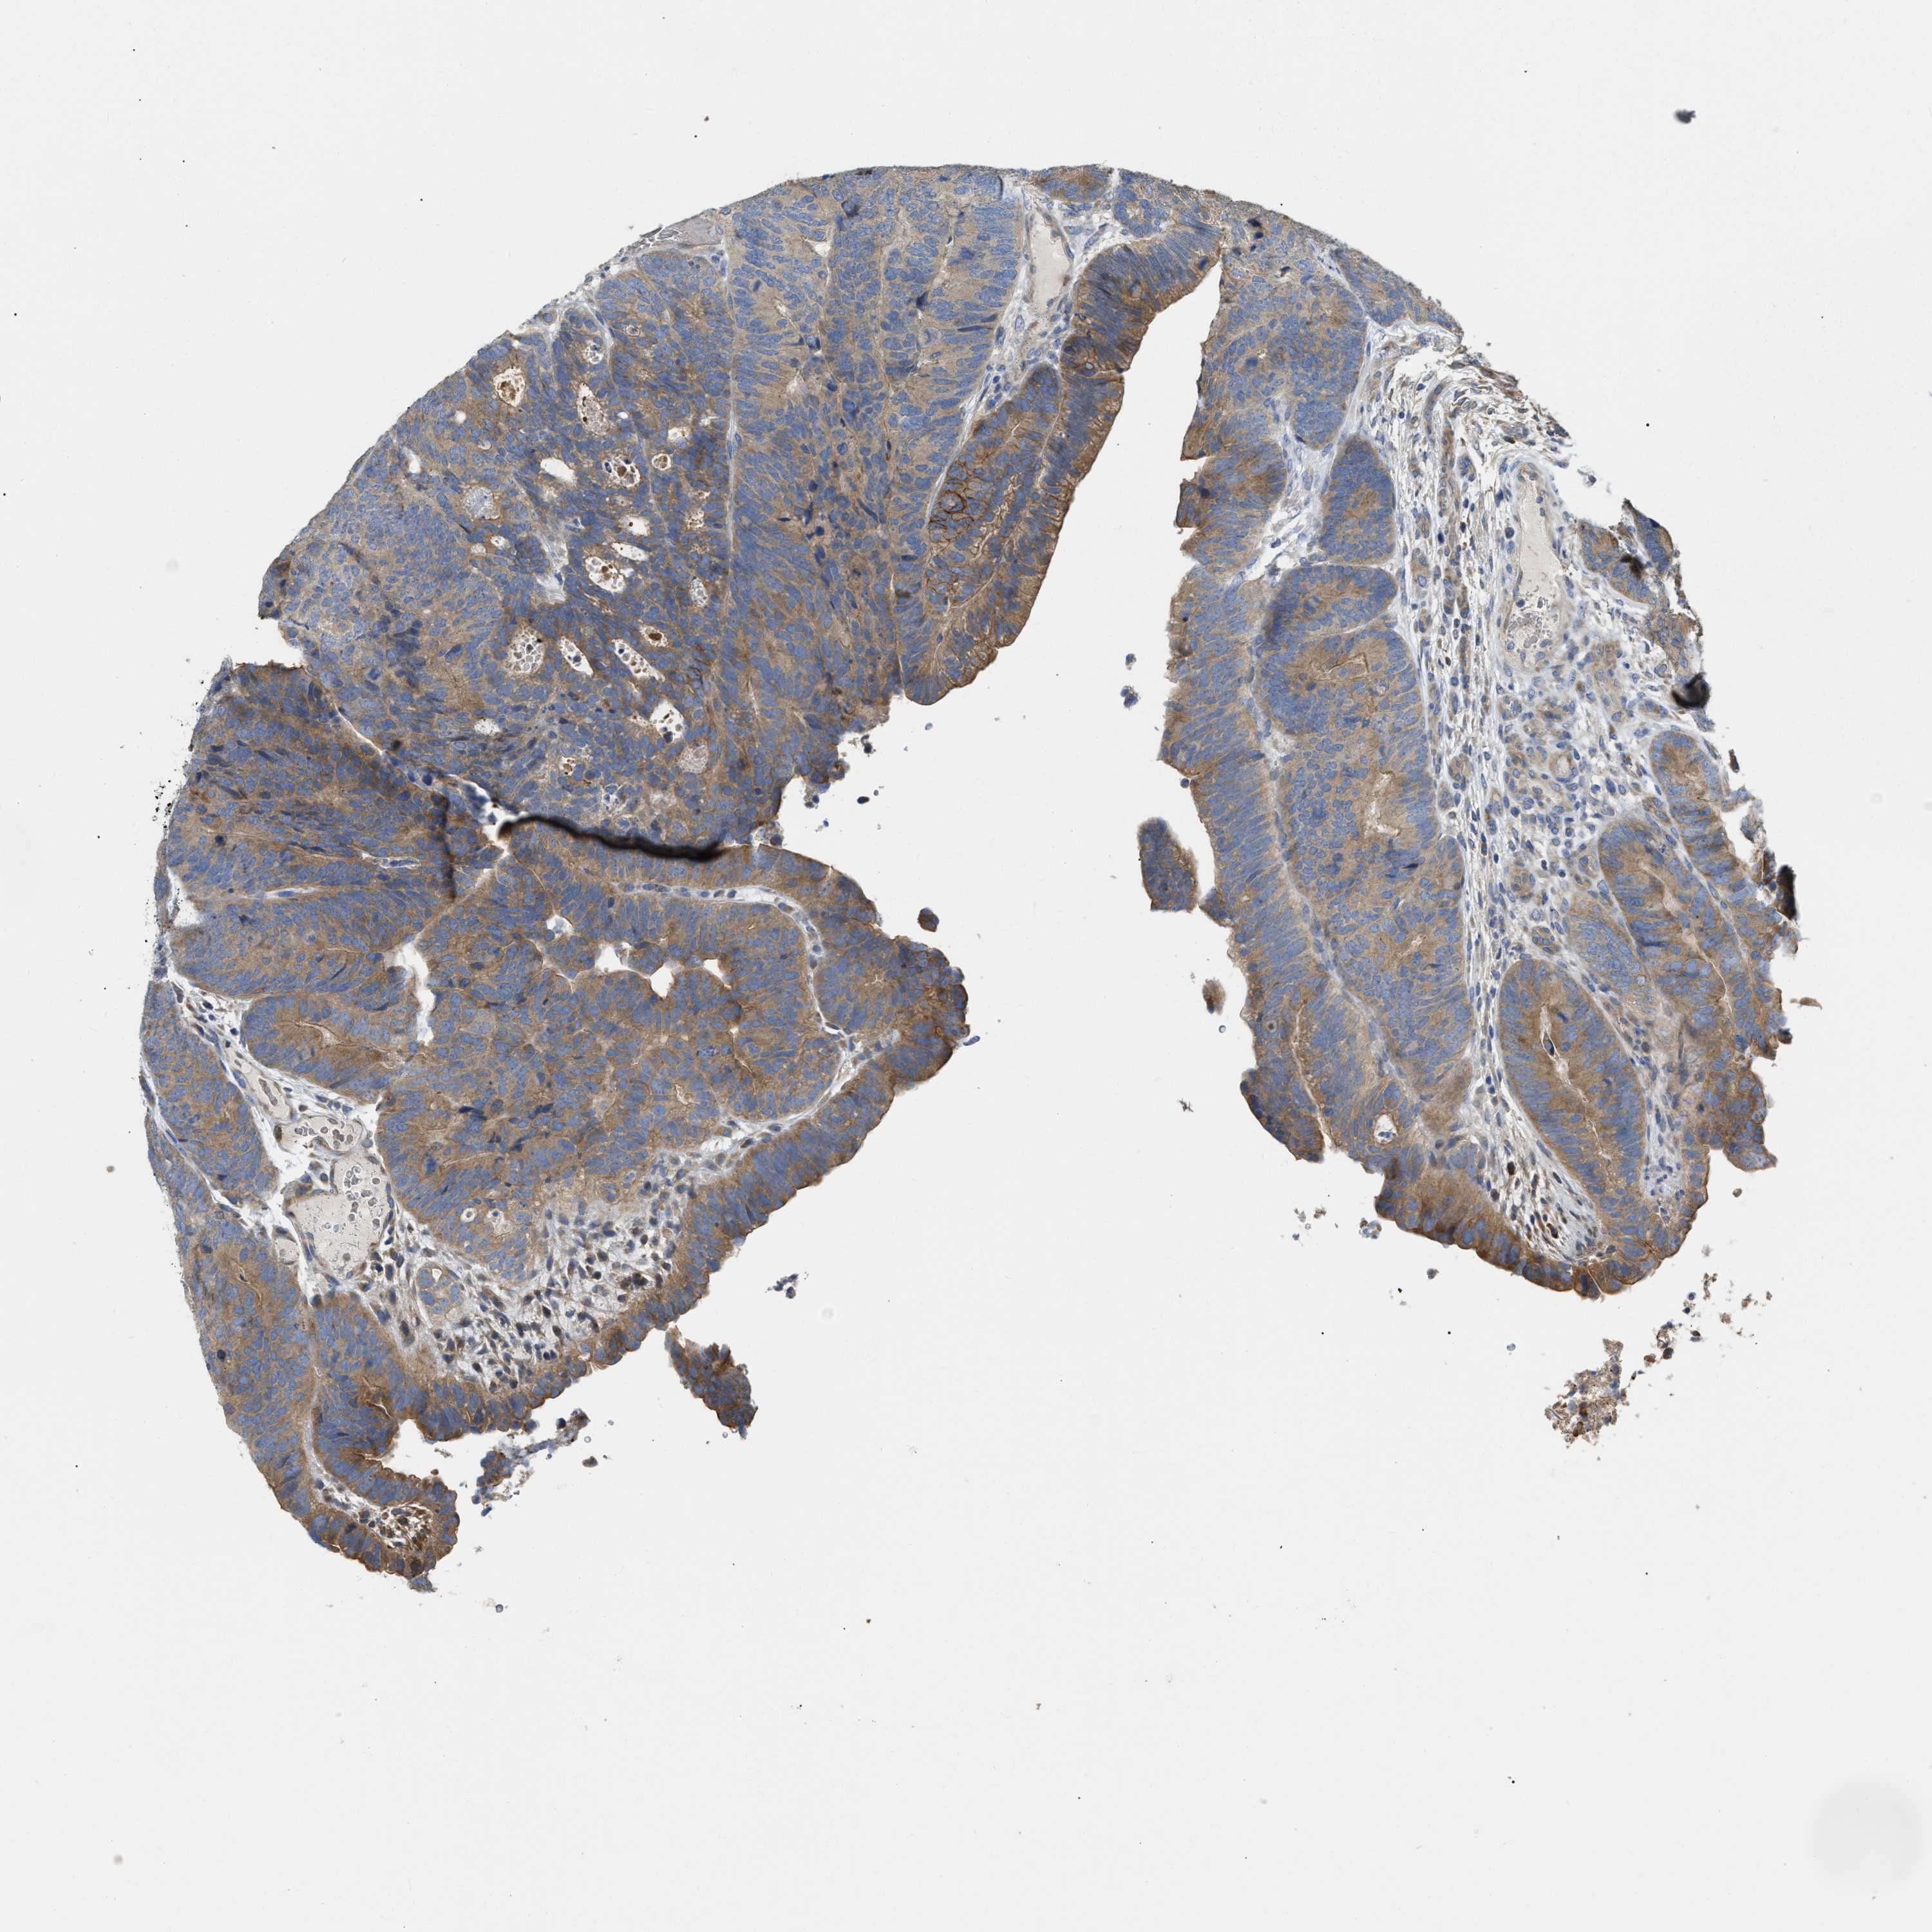

CANCER COLORECTAL CANCER Show tissue menu

Colorectal cancer

Colon adenocarcinoma